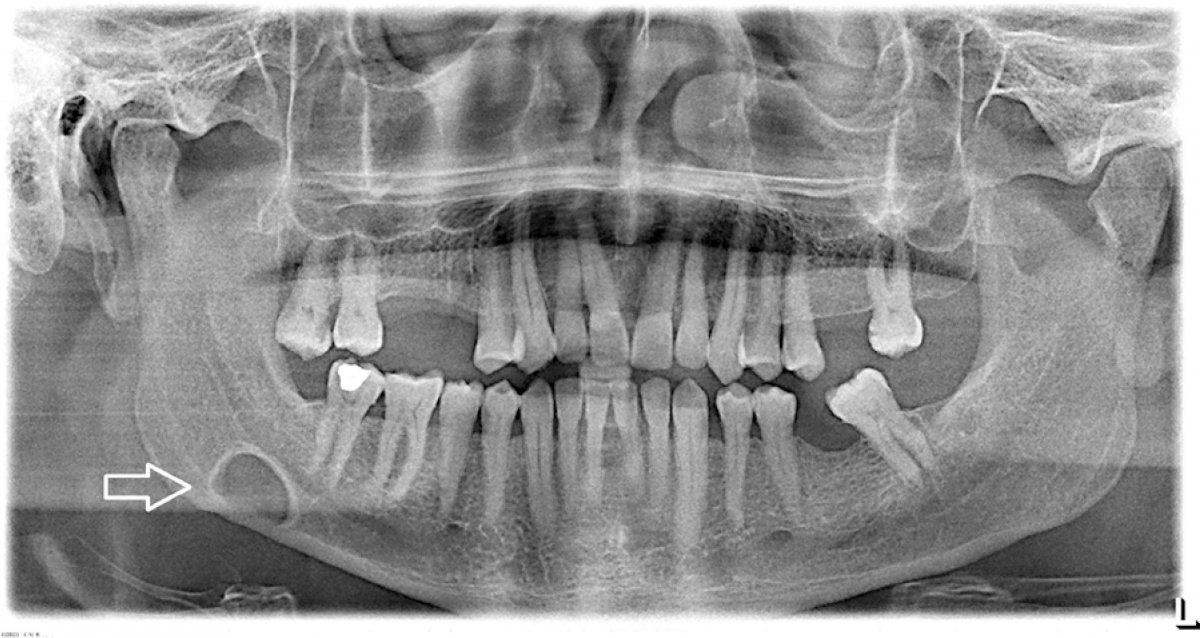

I did some plain research on teeth about the structure and some unusual silhouette deture.